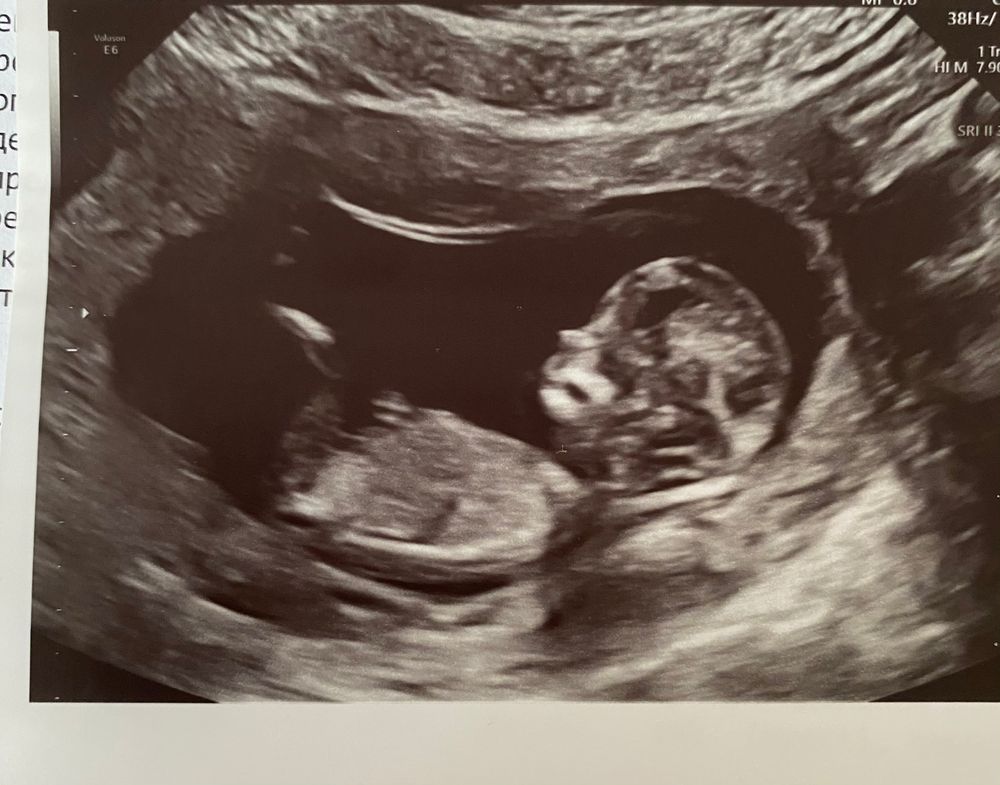

Узи 13 недель пол?!

Девочка, там у ножки пирожок виднеется)

Лариса, на самом деле на узи на пирожок не очень было похоже)

Я похожий вопрос задавала в 12, опрос делала, есть в дневнике. Из 120 ответивших половина сказали ещё рано/непонятно, а оставшиеся 50% разделились на 40 девочка и 10 мальчик. А узистка в 16 недель сказала: ничего не изменилось и уже не поменяется: мальчик)) как показывает практика, мальчики редко 'превращаются' в девочек, чаще наоборот